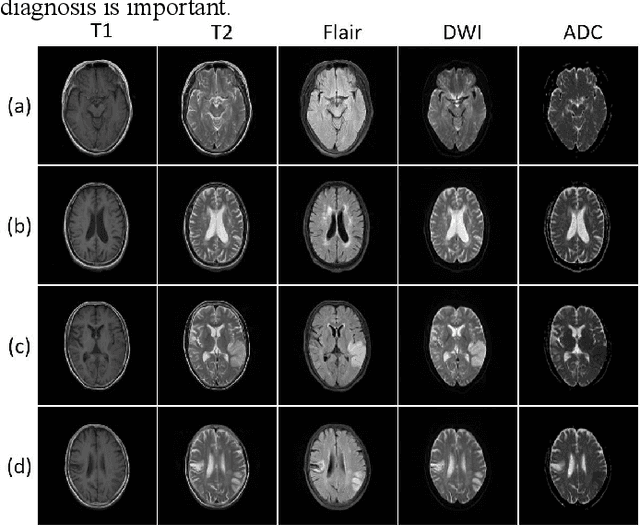

Abstract:Multi-contrast magnetic resonance (MR) image registration is essential in the clinic to achieve fast and accurate imaging-based disease diagnosis and treatment planning. Nevertheless, the efficiency and performance of the existing registration algorithms can still be improved. In this paper, we propose a novel unsupervised learning-based framework to achieve accurate and efficient multi-contrast MR image registrations. Specifically, an end-to-end coarse-to-fine network architecture consisting of affine and deformable transformations is designed to get rid of both the multi-step iteration process and the complex image preprocessing operations. Furthermore, a dual consistency constraint and a new prior knowledge-based loss function are developed to enhance the registration performances. The proposed method has been evaluated on a clinical dataset that consists of 555 cases, with encouraging performances achieved. Compared to the commonly utilized registration methods, including Voxelmorph, SyN, and LDDMM, the proposed method achieves the best registration performance with a Dice score of 0.826 in identifying stroke lesions. More robust performance in low-signal areas is also observed. With regards to the registration speed, our method is about 17 times faster than the most competitive method of SyN when testing on a same CPU.